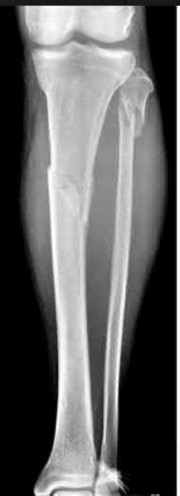

Question 19:

A 28-year-old male sustains a closed comminuted tibial shaft fracture. Two hours post-injury, he develops severe leg pain unyielding to narcotics. His blood pressure is 120/80 mmHg. Intracompartmental pressure monitoring is performed. Based on current guidelines, which measurement dictates an emergent 4-compartment fasciotomy?

Correct Answer: Delta pressure (Diastolic BP - Compartment Pressure) < 30 mmHg

Explanation:

Acute compartment syndrome is classically defined by tissue hypoperfusion. The absolute compartment pressure is less reliable than the differential pressure (Delta P). A Delta P (Diastolic Blood Pressure minus Compartment Pressure) of less than 30 mmHg is an absolute indication for emergency fasciotomy, as capillary perfusion gradient is lost when tissue pressure approaches the diastolic pressure.